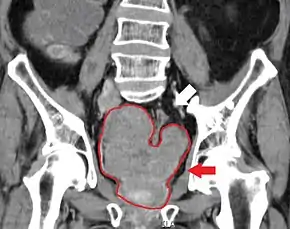

Sclerosis of the bones of the thoracic spine due to prostate cancer metastases (CT image)

Sclerosis of the bones of the pelvis due to prostate cancer metastases